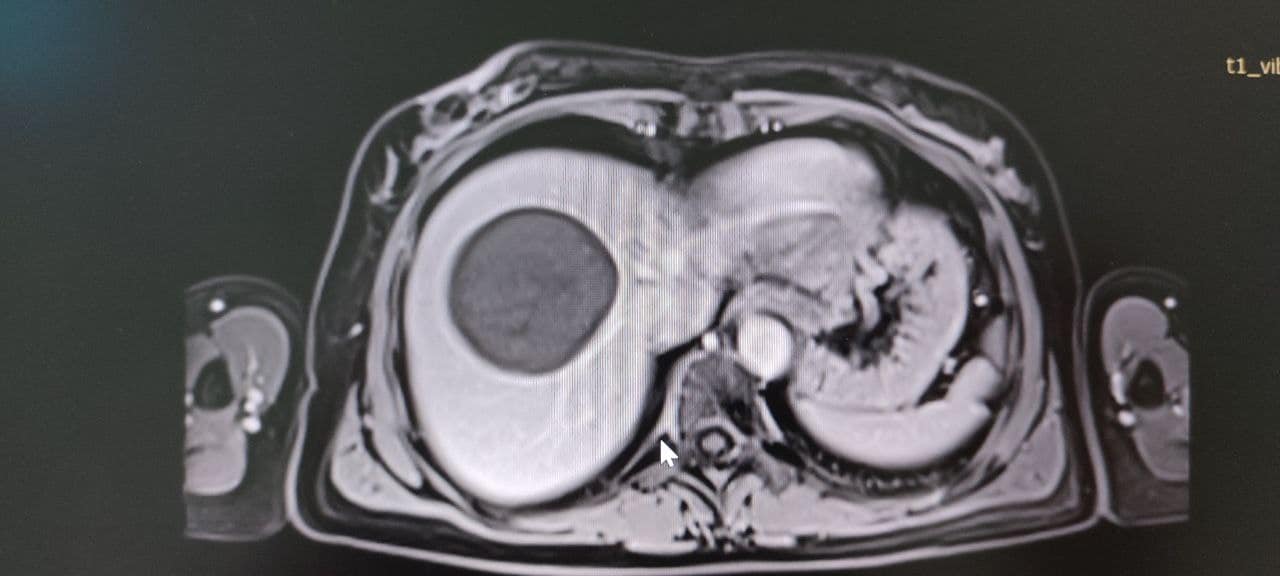

У Володимирське ТМО поступила 50-річна жінка зі скаргами на тиснення і біль у правому підребер’ї. У неї діагностували небезпечне і рідкісне захворювання – ехінококову кісту, яку хірургічно видалили.

Паразитарна кіста в печінці нагадує навколоплідний міхур, всередині якого дозрівають личинки ехінокока. Новоутворення поступово зростає і часом досягає гігантських розмірів (до 50 см у діаметрі).Ехінококозом може захворіти будь-яка людина, імунітету проти цієї хвороби немає. Хвора людина для людей, що її оточують, небезпеки не становить.